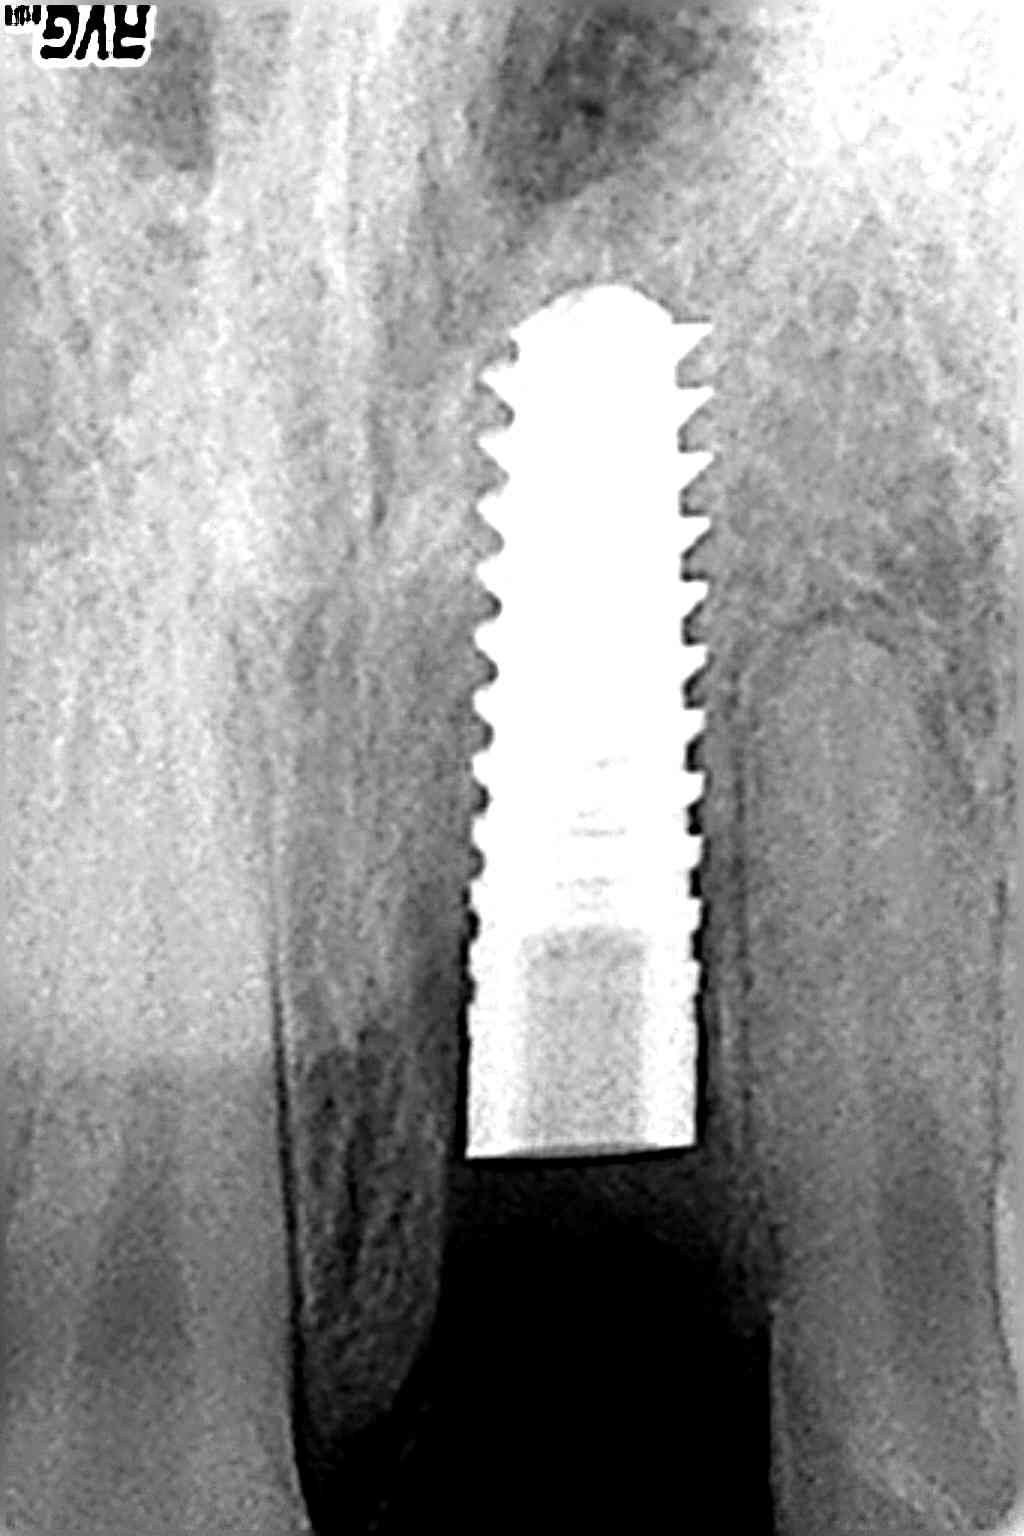

Dopo aver spiegato al paziente le varie possibilità protesiche, ci si orienta per intervento di chirurgia implantologica in posizione 2,1 con relativa corona. Si valuta la TC dental scan per le misure implantari, decidiamo di intervenire al più presto per evitare ulteriore perdita di tessuto, dalla prima visita all’inserimento dell’impianto passano tre settimane.(foto 3,4,5) L’intervento viene eseguito con un lembo a tutto spessore nella parte più coronale, e a spessore parziale nella parte più apicale cercando di lasciare connettivo adeso alla corticale vestibolare, sezionando fibre muscolari per una maggior trazione del tessuto molle. Il sito ricevente viene sottopreparato, l’impianto di lunghezza 14mm diametro 4mm viene serrato con chiave dinamometrica a 40 N, si posiziona abutment in titanio serrato manualmente,si procede alla costruzione di corona provvisoria in policarbonato, rifinita ed adattata in sottoclusione, - Carico Non Occlusale Immediato (CNOI) (immediate non occlusal loading): sutura del lembo riassorbibile.si dimette il paziente con le terapie del caso.(foto 6,7,8,9,10,11) Controllo ad una settimana, e alla seconda settimana rimozione della sutura.(foto 12) La corona definitiva in zirconio ceramica su abutment in zirconio viene posizionata intorno al quinto mese dall’intervento.(foto 13,14)